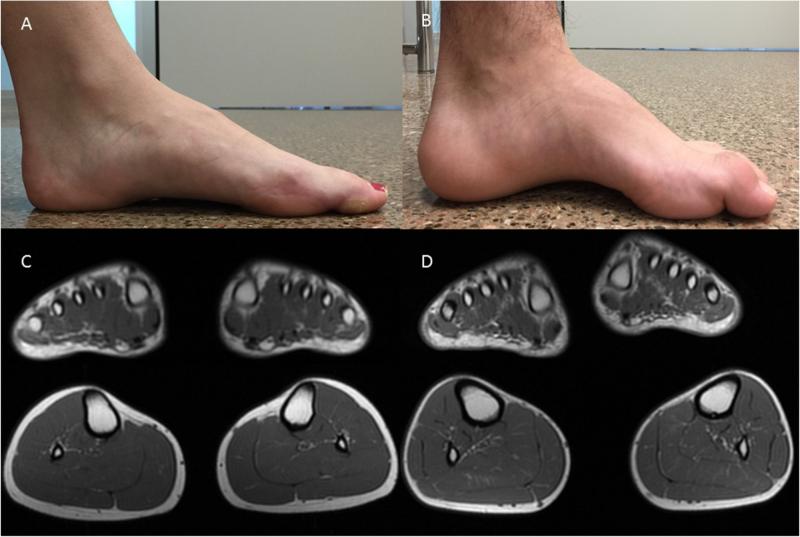

Charcot-Marie-Tooth Disease is a hereditary neurological disorder that affects the peripheral nerves, leading to muscle weakness and atrophy in the legs, hands, and feet. The market for Charcot-Marie-Tooth Disease products includes various treatment options such as medication, physical therapy, orthopedic devices, and surgery. These products aim to alleviate symptoms, slow down disease progression, and improve the quality of life for patients.